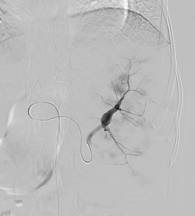

朱××,男,45岁,双侧股骨头坏死,左侧髋关节疼痛明显,不能独立行走,需使用止痛药物(图1,MR)。介入治疗术中造影(图2a)示:股骨头供血动脉分支稀疏,远端痉挛、股骨头骨质内无明显分支动脉血管;治疗后(图2b)造影见股骨头供血动脉分支血管明显增多,远端可见达股骨头骨质内,原髋关节疼痛消失,自行行走出院。

图1 图2a 图2b